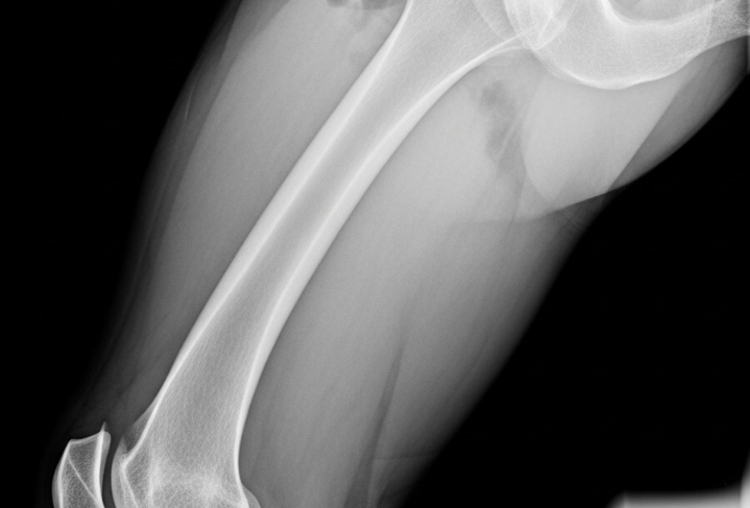

O caso remonta a dezembro de 2013, quando o paciente fraturou o fêmur e foi internado no Hospital da Unimed. Ele permaneceu 13 dias sem exames pré-operatórios essenciais. A cirurgia, realizada tardiamente, foi marcada por graves complicações, incluindo paradas cardíacas, uso de desfibrilador, queimaduras e necessidade de hemodiálise e UTI.

Relatórios médicos posteriores apontaram erros técnicos no procedimento inicial, como a má colocação de haste e fratura do fêmur, resultando em sequelas permanentes como encurtamento do membro, dor crônica e limitação funcional.